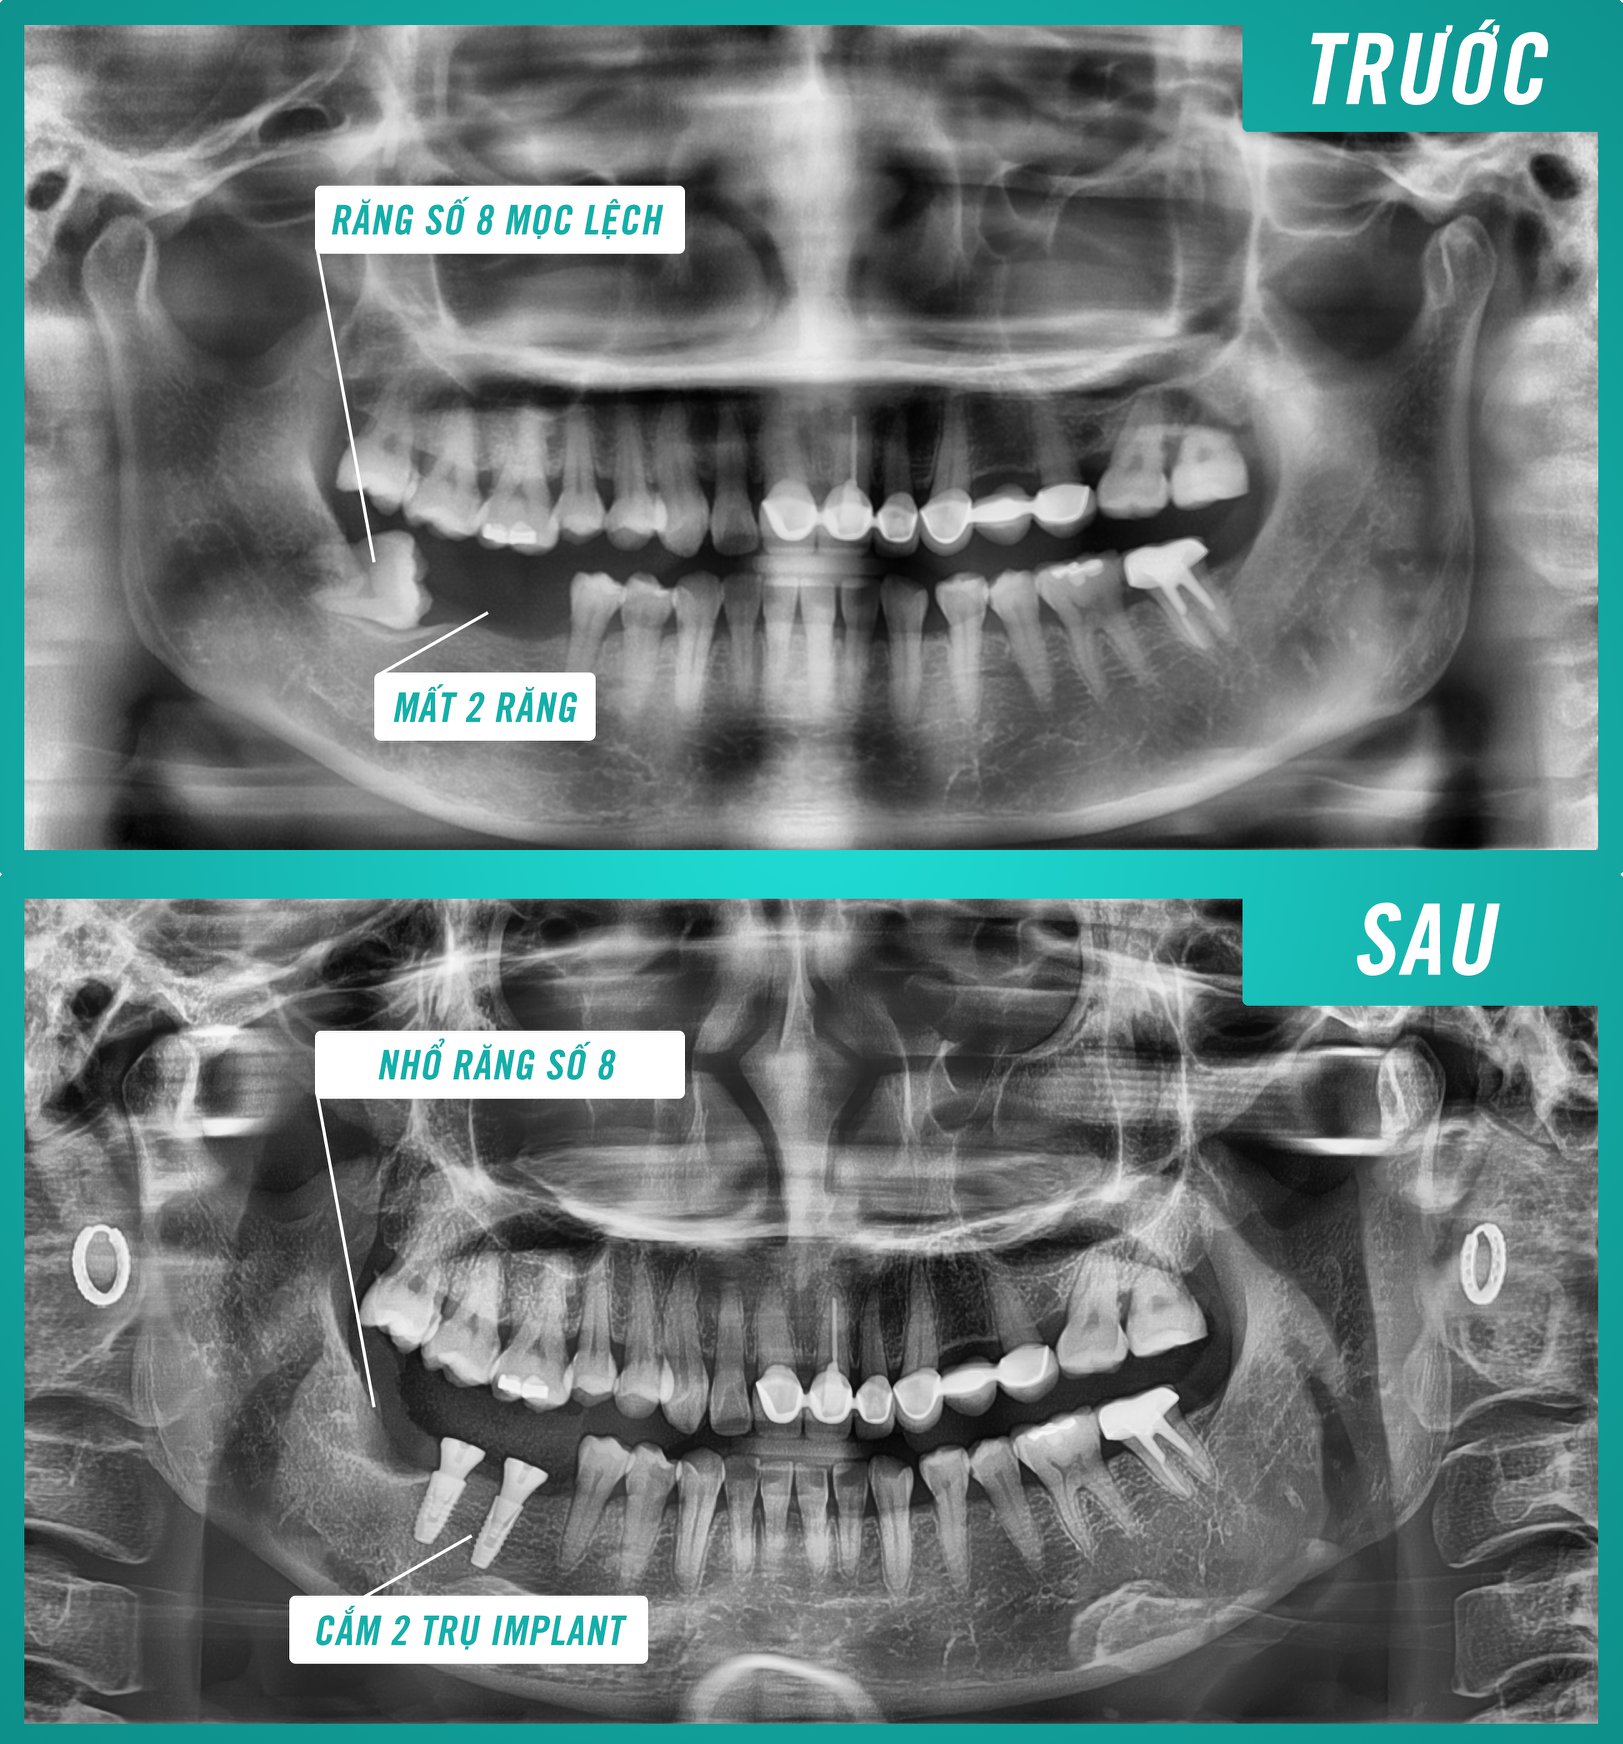

a/ Thăm khám, tư vấn và chụp X-Quang

- Khám tổng quát khoang miệng, tình trạng răng, nướu và sức khỏe của bệnh nhân. Nếu phát hiện bệnh lý thì cần được hỗ trợ điều trị trước khi tiến hành cấy trụ.

- Chụp X-quang kiểm tra mật độ xương, độ dày xương hàm.

- Tính toán chính xác độ dài, kích cỡ, đường kính và số ren cho trụ implant tương thích với đặc điểm cấu tạo xương hàm bị mất răng